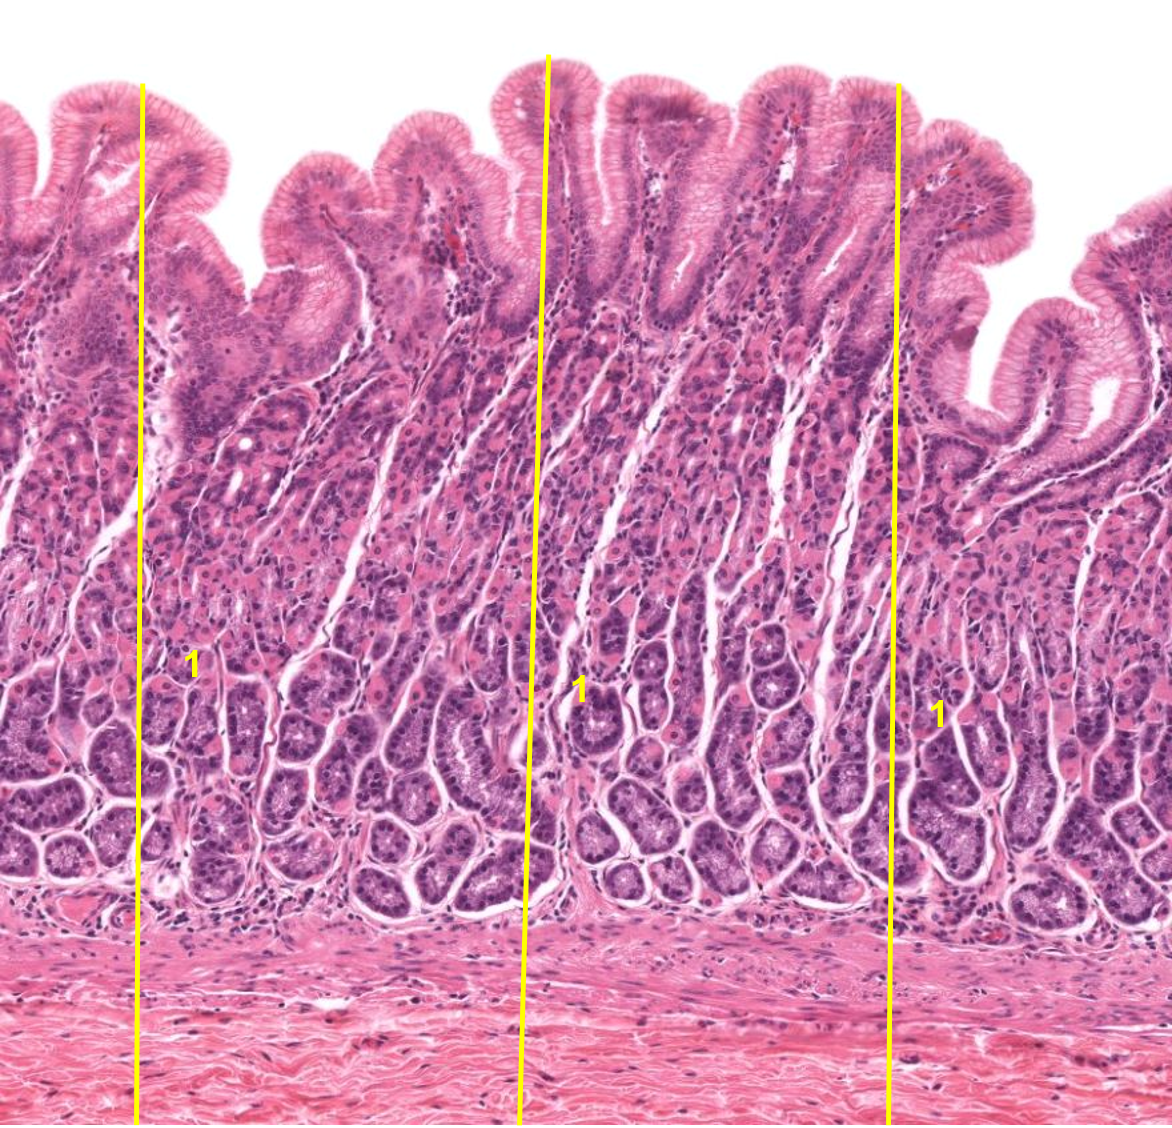

1: intestino delgado / Duodeno

2: Vilosidades

1: Íleon

2: Velocidades